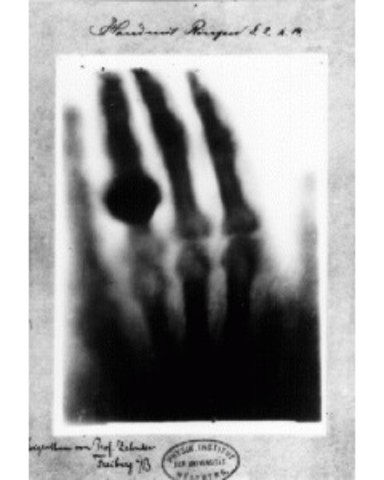

• Rayos X

Rayos X

Wilhelm Roentgen descubre los rayos X y toma la primera imagen de la mano de su esposa.